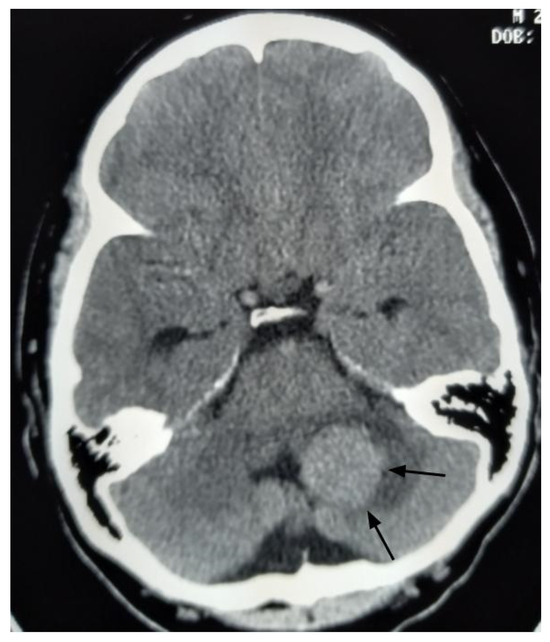

A 26-year-old male presented to the emergency department with imbalance and severe headaches. Magnetic resonance imaging (MRI) was not available at the time of presentation. Due to obstructive hydrocephalus, emergent surgery was performed the same day using only a head computed tomography (Figure 2). The tumor was internally debulked to facilitate GTR. Pathology confirmed a fourth ventricular CPP exhibiting rare mitoses (up to 1 per 10 high-power fields) and a Ki-67 index of 5%. Postoperative brain MRI revealed no residual tumor or additional lesions.

Figure 2.

Axial head computed tomography with contrast image, performed before the initial surgery, reveals a large enhancing mass in the left cerebellum (black arrows).